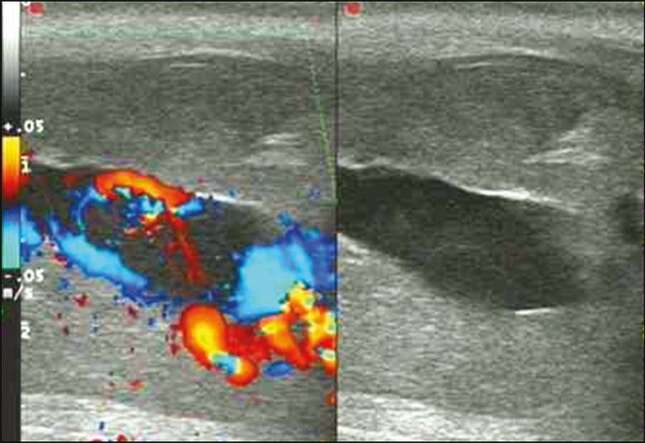

En el caso del paciente en Delhi, tal y como informan en el artículo de BMJ, en principio no representaba peligro. Los médicos crearon una derivación en forma de T (usando un escalpelo a través de la cabeza del pene para crear un “orificio de escape” para la sangre atrapada) con el fin de que la hinchazón disminuyera.

Sin embargo, al día siguiente de su llegada al centro médico la cabeza del miembro se decoloró y comenzó a volverse negra. Cuatro días después del inicio de la erección, el hombre fue trasladado al Departamento de Urología del King George’s Medical University, espacio donde fue examinado.

Y es que la gangrena, donde una pérdida de suministro de sangre causa la muerte del tejido, continuaba extendiéndose sobre el pene del paciente. Como explica el doctor Saqib Mehdi en el informe del caso:

El color negro del glande del pene se hizo más intenso al día siguiente. Y una línea clara de demarcación se hizo visible entre ella y el eje del pene.

Fue en este momento cuando el equipo médico decidió que para detener la diseminación de la gangrena tendrían que realizar una glansectomía (amputación de la cabeza del pene).